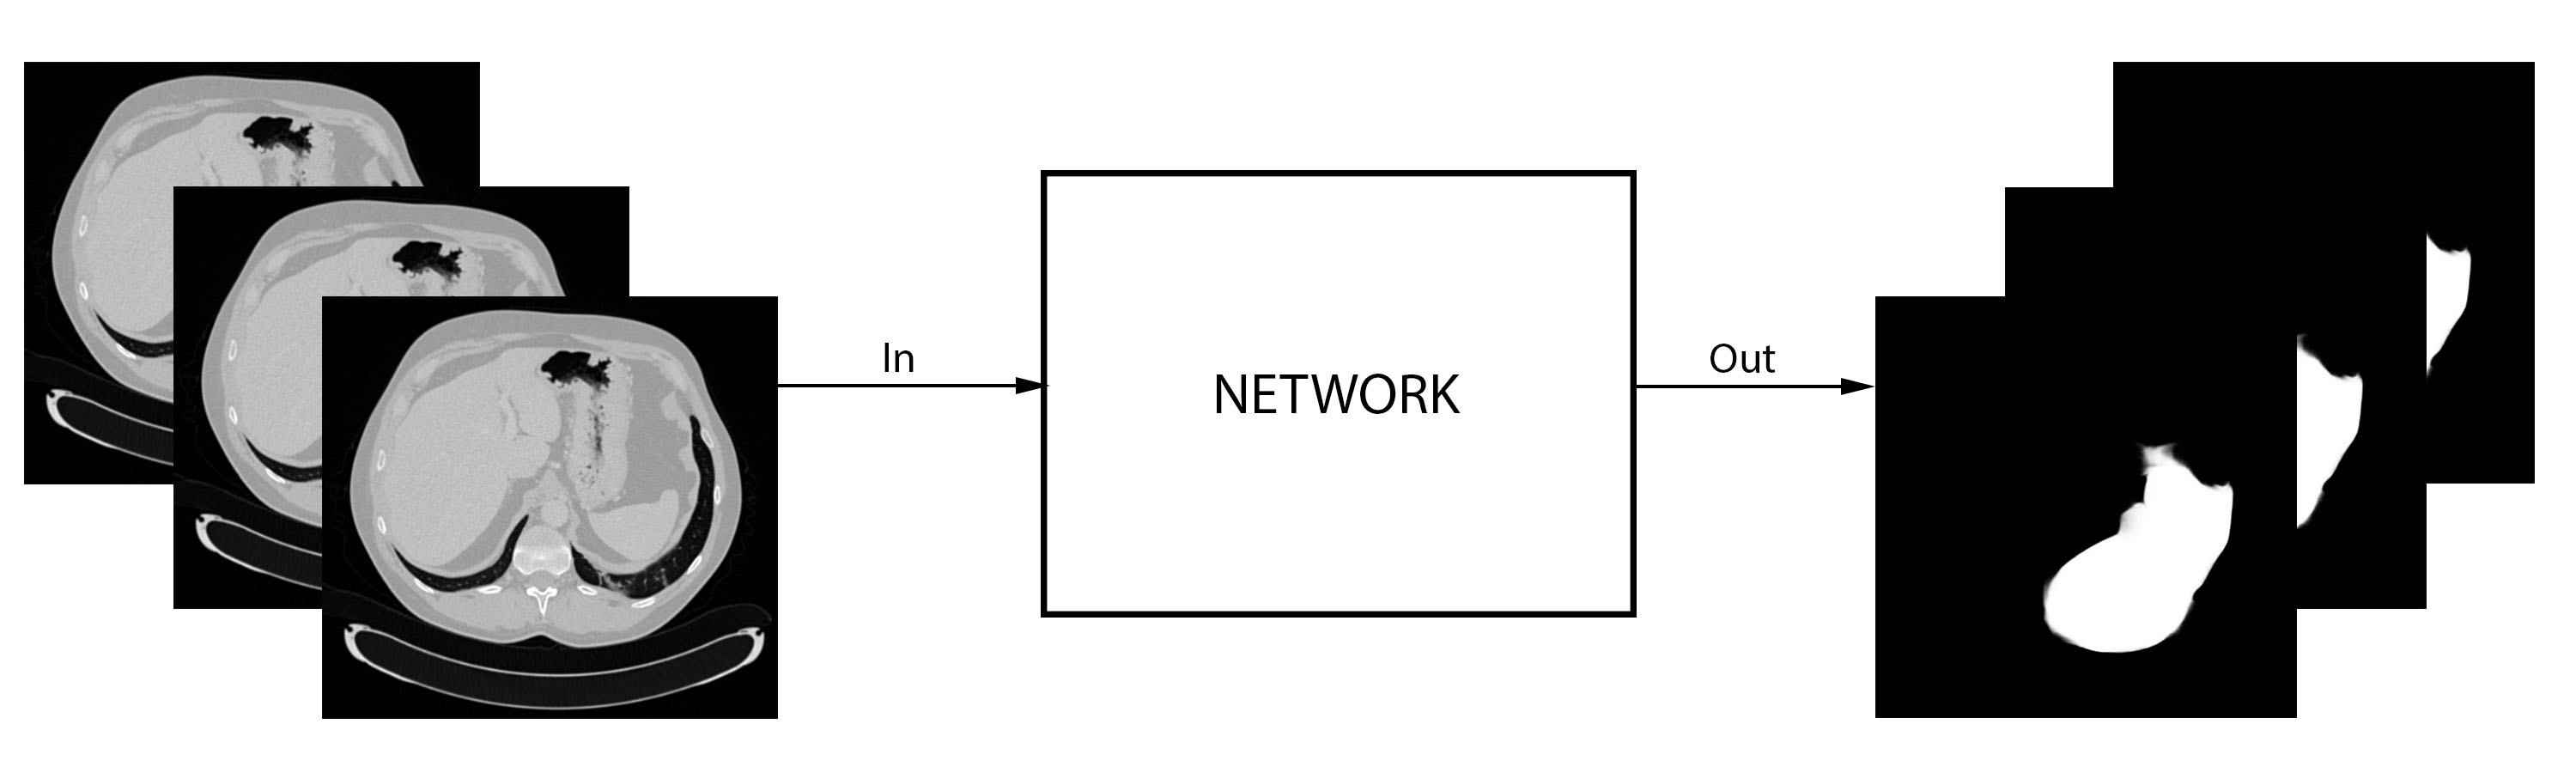

Originally the algorithm parsed the data as if the slices were independent, while in fact they have a strong 3D coherence. Also, the algorithm was pretrained with Imagenet, and it uses 3 channel images for training - RGB (Red, Green, Blue). Hence, as shown in Figure 3.6, the three channels can be fed simultaneously three slices of the volume analyzed, one at each RGB channel (2.5D approach), while during testing only the central output slice is kept. Figure 3.6 refers to the liver segmentation, but the approach is the same for the lesion segmentation network.